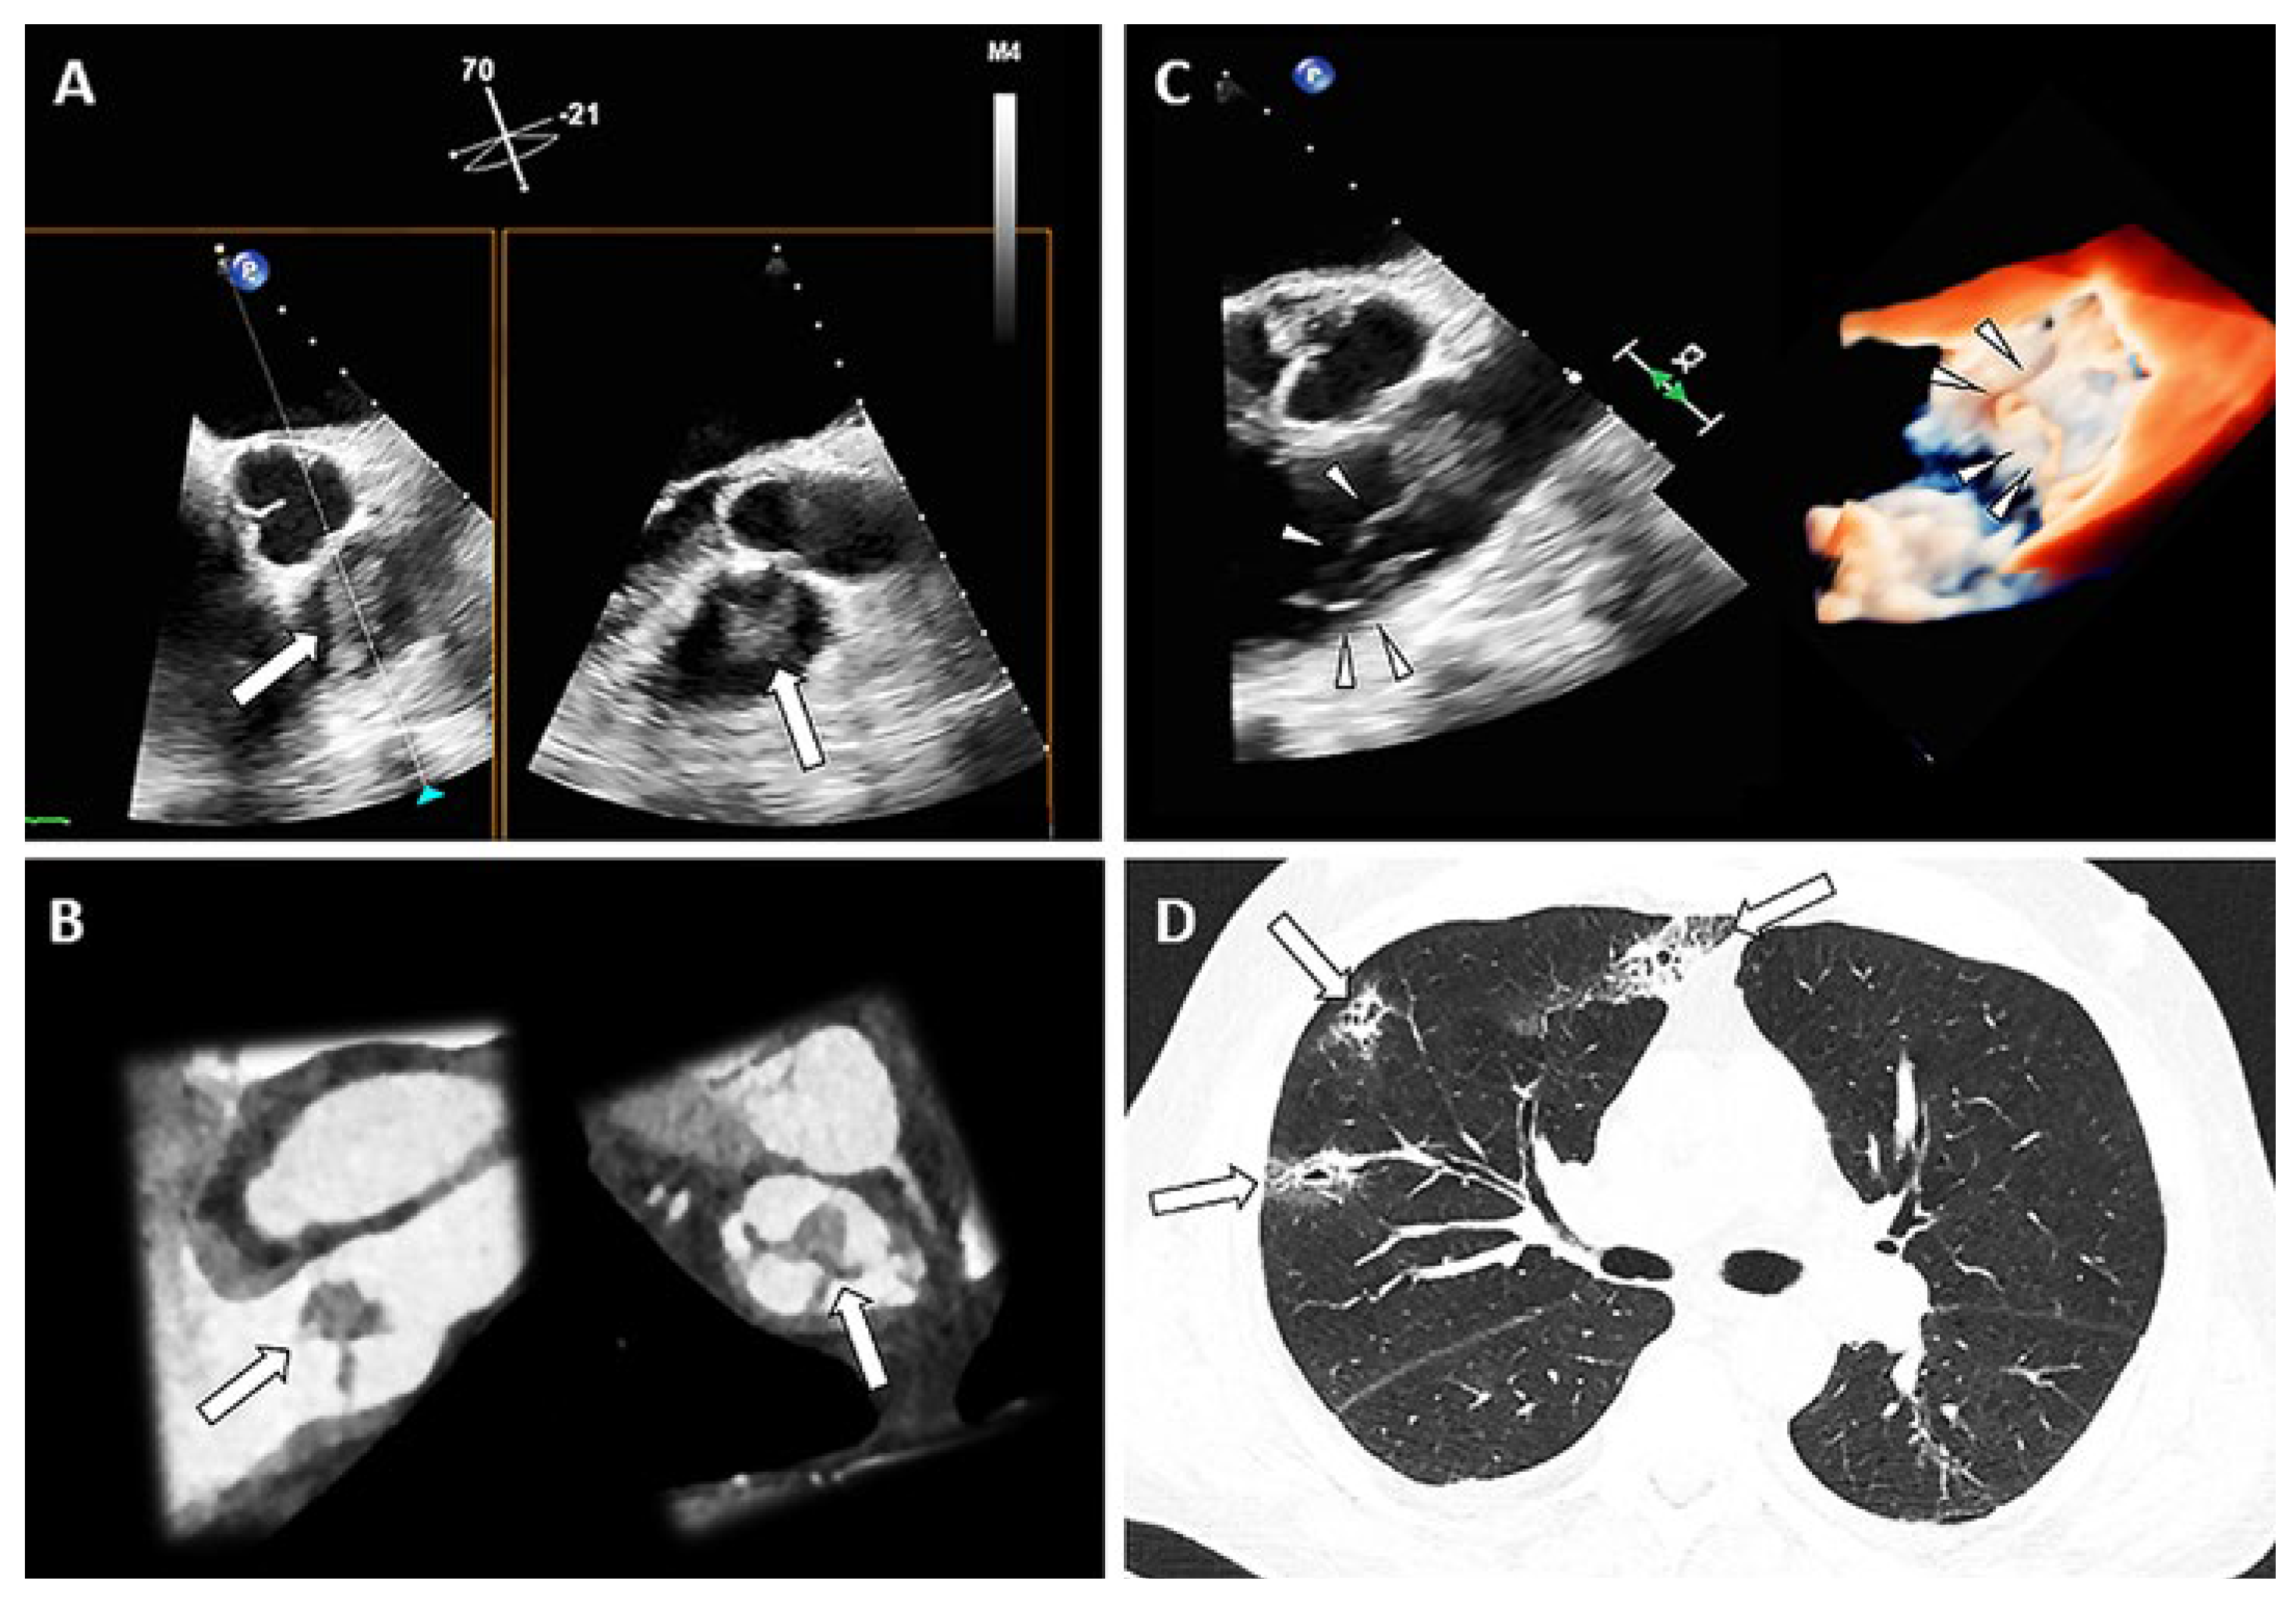

A 74-year-old male patient presented with malaise, fever, chills, and palpitations for the past five days. On admission, he was afebrile, hypotensive and tachycardic. Laboratory testing showed: leucocytosis of 20.1 Giga/l (ref. 2.6– 7.8 Giga/l), C-reactive protein of 278 mg/l (ref. <5 mg/l), procalcitonin of 4.64 µg/l (ref. <0.5 µg/l), increased d-dimer level of 29 372 ng/ml (ref. <500 ng/l). Transthoracic echocardiography revealed a normal ejection fraction with D-shaping and estimated systolic pulmonary arterial pressure of 65 mm Hg; no signs of endocarditis were detected. Due to the signs of right ventricular overload and severely impaired renal function at this time lung perfusion scintigraphy (SPECT/CT) was performed, which showed multiple small consolidations, suggesting septic emboli (Figure 1, arrows, panel D). The suspicion of right heart endocarditis triggered transoesophageal echocardiography, which exhibited masses on all cusps of the pulmonary valve, also depicted in a follow-up CT (arrows, panel A and B, corresponding planes). Furthermore, a large (19 × 12 mm), mobile, ribbon-shaped vegetation was protruding into the right ventricular outflow tract (arrow heads, panel C, 2-dimensional and 3-dimensional; 2D: video 1, 3D: video 2); the function of the pulmonary valve was normal. All other valves were free of vegetations. Blood cultures showed growth of Staphylococcus aureus. After interdisciplinary discussion and in line with guideline recommendations, conservative treatment with flucloxacillin was started.

Figure 1. Masses on the pulmonary valve (A. TEE, B. CT), ribbon-shaped vegetation in TEE (C), septic emboli in CT (D).